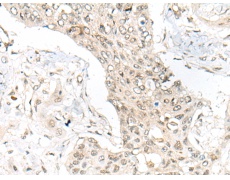

IHC positive control: |

Human prostate cancer and human gastric cancer |